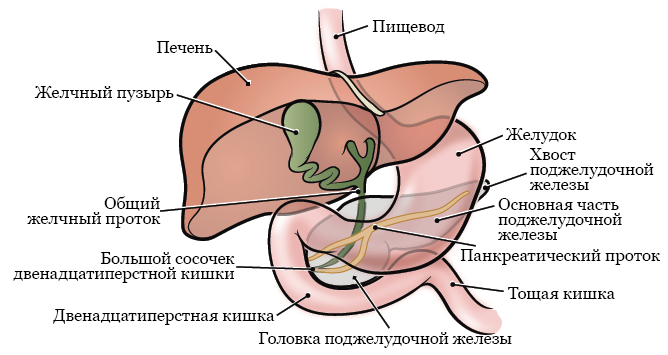

Анатомия и особенности Гартманова кармана желчного пузыря